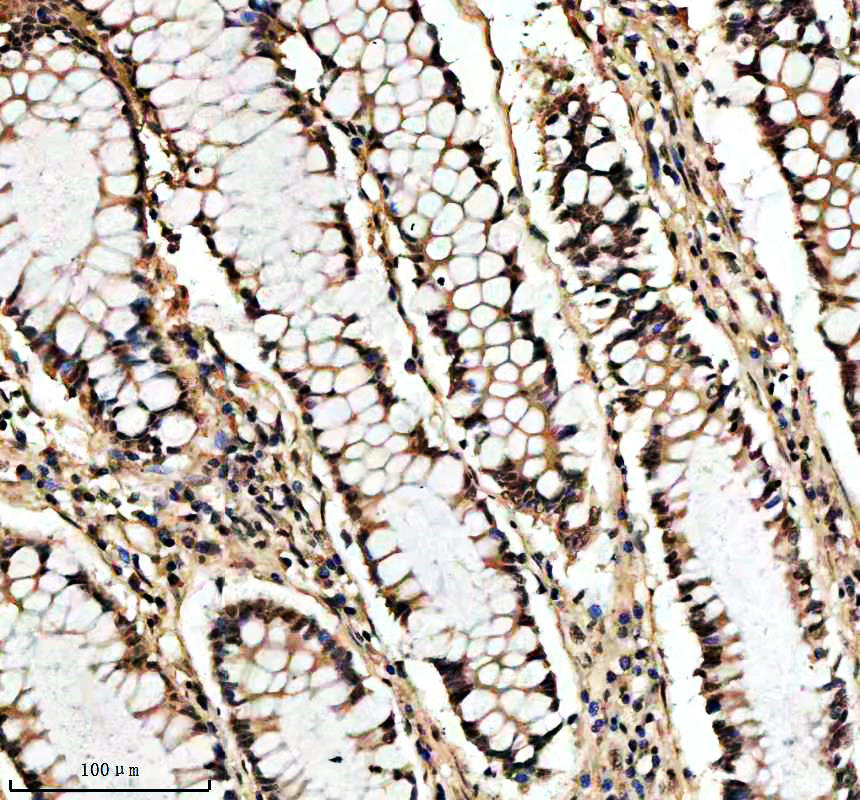

IHC analysis of SHP2/PTPN11 using anti-SHP2/PTPN11 antibody (BM4588) .

SHP2/PTPN11 was detected in a paraffin-embedded section of human colon tissue. The tissue section was incubated with rabbit anti-SHP2/PTPN11 Antibody (BM4588) at a dilution of 1:200 and developed using HRP Conjugated Rabbit IgG Super Vision Assay Kit (Catalog # SV0002) with DAB (Catalog # AR1027) as the chromogen.